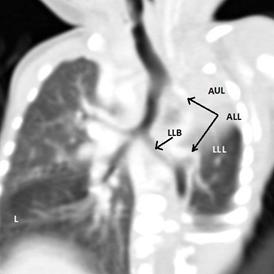

Figure 1.2 CT chest (lung window).

A: absent Rt. Lung, B: Lt. upper and lower lobe bronchi, C: dextroposition of heart - displaced in to the Rt. Hemi thorax, L: hyperinflation of contra lateral lung

Figure 2.3 CT chest (reconstructed).

AUL: absent Lt. upper lobe, LLB: Lt. Lower lobe bronchus, ALL: aberrant artery from the aortic arch supplying Lt. lower lobe, L: hyperinflation of contra lateral lung AA1: aortic arch 1, AA2: aortic arch 2.